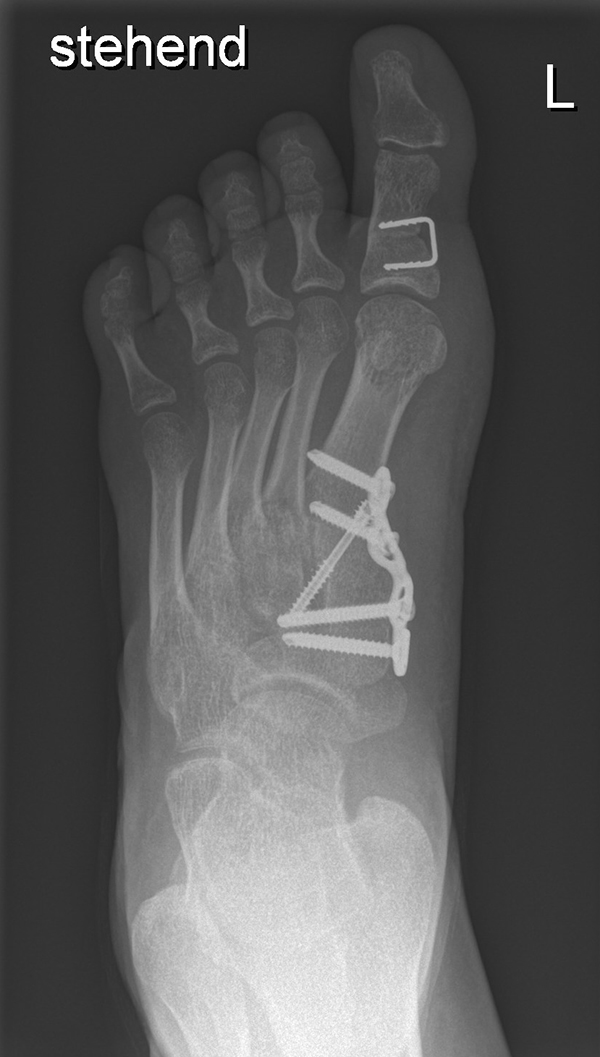

Abb. 40 a-f: Kompletter klinischer und radiologischer Verlauf eines schweren Ballenhohlfußes: Bild im Stand mehrere Ansichten sowie radiologische Diagnostik präoperativ (a), percutane Ablösung der Plantarfaszie als ersten operativen Schritt (b), radiologisch sichtbare Osteot0mien MT I-V sowie klinisches Ergebnis intraoperativ (c-d), klinische Gegenüberstellungen der präoperativen Fehlstellung und der postoperativen Korrektur (e); zweites Beispiel eine spastische Hohlfußfehlstellung im prä- und postoperativen klinischen Verlauf (f).

Zum Lesen der Bildbeschreibung und zur Vollansicht bitte die Bilder anklicken. Bilder: A. Helmers.